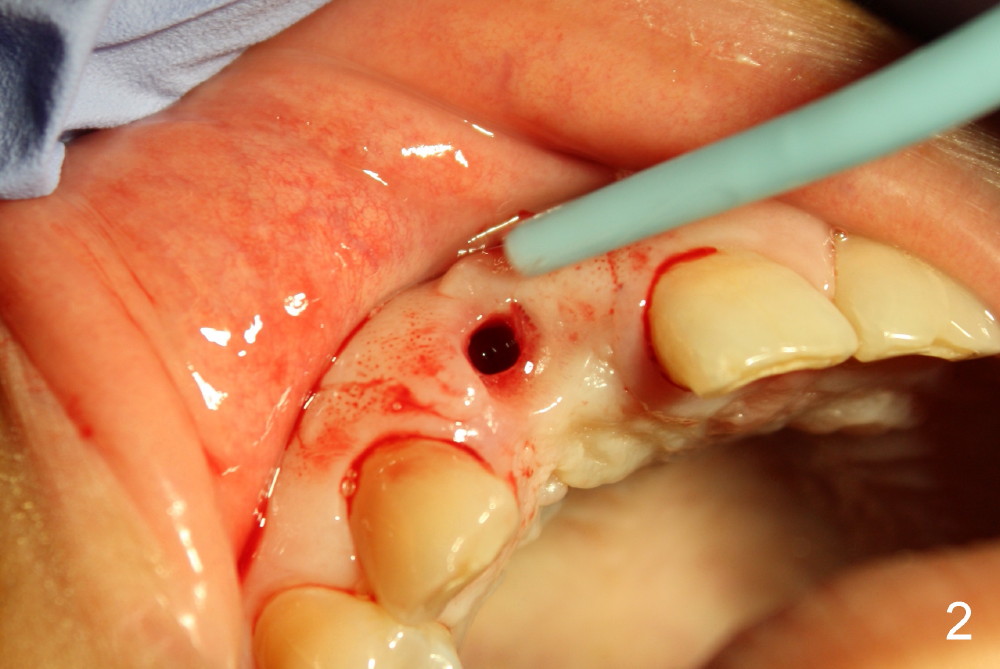

Malpositioned implant in the anterior region is cosmetically unacceptable. Immediate provisional allows us to note the issue immediately. The crown looks too long. Secondly, the provisional is easily dislodged, since the buccal aspect of the angled abutment is over trimmed (Fig.1). The implant (3.8x14 mm), which has been placed 3.5 months, is unexpectedly easily removed by reverse torque (Fig.2). The buccal wall is intact, whereas there seems to be enough bone lingually to place an implant. A small incision is made (Fig.11) so that the gingival tissue can be transferred buccally (Fig.12) and the immediate implant is to be placed palatally (Fig.13 white circle). There is no difficulty forming osteotomy in the palatal wall, followed by inserting 4.5x20 mm tap at the depth of 17 mm (Fig.3,5). But the tap is not palatal enough (Fig.4). By removing more palatal bone, the 4.5x17 implant (Fig.6) appears to be placed palatally enough for restoration (Fig.7; A: abutment; *: buccal gap). The biggest problem is that the palatal flap (Fig.7 arrowheads) cannot be pushed buccally; instead remains palatally. This leads to buccal tissue deficiency (Fig.8). Connective tissue graft is offered, but declined. The patient insists that she has low smile line. Following immediate provisional, mixture of allograft and synthetic graft is placed in the buccal gap (Fig.9). The overbuilt graft is held in place by perio dressing.